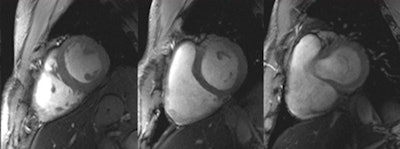

Set of six (top and bottom) 2D CINE FLASH images of the beating human heart derived at systole from a series of 12 short-axis views ranging from the apex to the base of the heart (in-plane resolution [1 x 1] mm2, slice thickness of 4 mm, acceleration factor = 2, GRAPPA). A 2D 16-channel transmit/receive radiofrequency coil array was used for signal transmission and reception.6 The images illustrate that a rather uniform intensity distribution was obtained across the entire heart.6Admittedly, the reports put forward by numerous pioneers and early clinical adopters are so far largely anecdotal. It is a fractal pattern, though, and a consistent story is starting to emerge -- a story worth following since its clinical implications feed into a broad spectrum of neurology, neuroscience, neuroradiology, radiology, cardiology, and other fields of clinical research. This story includes a chapter that comprises around 150 abstracts presented at the recent 20th annual meeting of the International Society of MR in Medicine (ISMRM) held in Melbourne, Australia, and more than 100 clinical research papers published since 2010.

It is no secret that the feasibility of 7-tesla MRI is not limited to the brain, but also can be beneficial for musculoskeletal and cardiac imaging. The requirements of cardiac MR at 7 tesla inspired recent advances in multichannel radiofrequency (RF) coil technology. This includes the move from cardiac optimized RF coils equipped with four transmit/receive channels only to 16 TX/RX channels configurations,6 and even 32 TX/RX channel versions.7

It has been shown that a larger number of elements, in conjunction with a 2D RF coil-array design, can improve image quality, as well as accelerated imaging performance.8 All these efforts culminated in images of the beating heart with a spatial resolution that is by an order of magnitude superior to that routinely available at 1.5 tesla.

These improvements offer detailed insights into cardiac anatomy and might provide means for a better understanding of the myocardial microstructure. Recognition of the benefits of the many channel RF coil configurations should help to eventually lead to a 7-tesla body RF coil design, though this is, for the moment, merely a vision. It is nonetheless a vision that offers the potential to inspire a further push toward body imaging at 7 tesla.